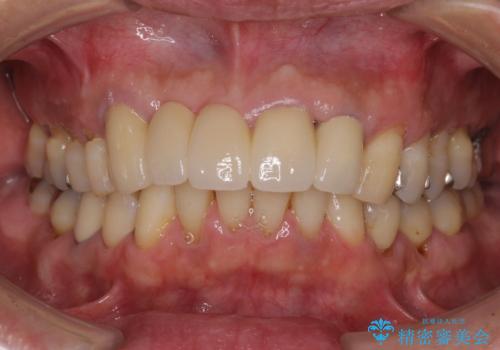

- 前歯のブリッジのせいで話しにくく、金属の縁などが露出して見栄えが悪いので、作り直したいとのことで来院された患者様です。

土台となる歯は根管治療の結果が良好ではないため、根管治療からやり直しをした後、オールセラミックブリッジにて補綴することとしました。

露出していた歯根や金属の縁が見えてしまい、人前で話すときの目線が気になっていらっしゃいましたが、歯肉の位置に縁を合わせてことで自然な仕上がりとなりました。

露出していた歯根が覆われるため、歯冠が長く見えてしまうことが懸念されましたが特に気になることはなく、患者様には大変満足していただきました。